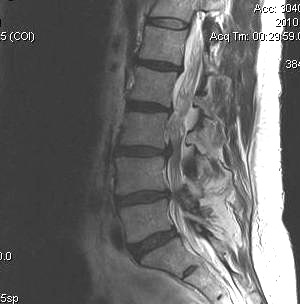

MRI

T2 Sagittal - myelogram

T1 Axial - see nerve root against white fat

DDx

Infection / Tumour / Fracture